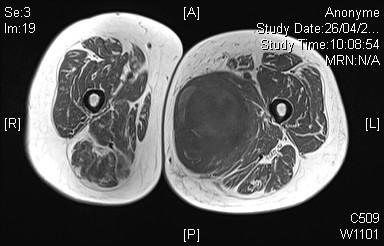

Néanmoins, c’est l’IRM qui est l’examen de référence. Sa version injectée permet de mieux distinguer lipomes, kystes synoviaux, tumeurs à cellules géantes, tumeurs nerveuses ou encore contenant une composante myxoïde (fig. 2 et 3). Mais, dans la majorité des cas, aucun diagnostic de certitude ne peut être obtenu à ce stade et la biopsie sera nécessaire avant d’entreprendre le traitement (fig. 1).